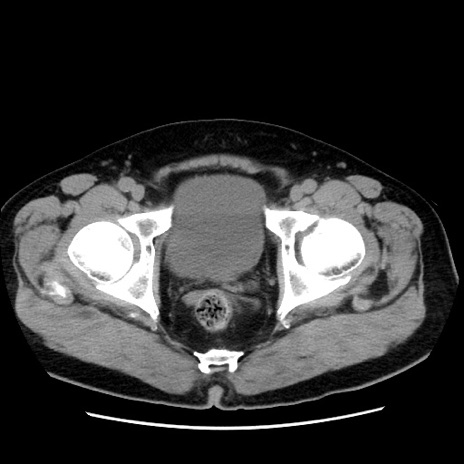

冠状断像

【症例】 70歳代男性

【主訴】 腹痛、嘔吐

【現病歴】 約1ヶ月前より間欠的に腹痛と嘔吐あり、当院消化器内科を受診したところCTで多発する肝臓のLDAを指摘され、精査中であった。以降は消化器症状は安定していたが、2日前より嘔気と腹痛があり、同日より排便・排ガスが消失した。改善認めず、 本日、救急外来を受診した。

【既往歴】 大腸ポリープ切除後。

【身体所見】意識清明・会話良好、BT 36.3℃、BP 127/80mmHg、 P 80bpm、腹部:膨満あり、平坦・軟、上腹部正中および下腹部正中に圧痛あり、反跳痛なし、筋性防御なし。

【データ】WBC 7200、CRP 0.77